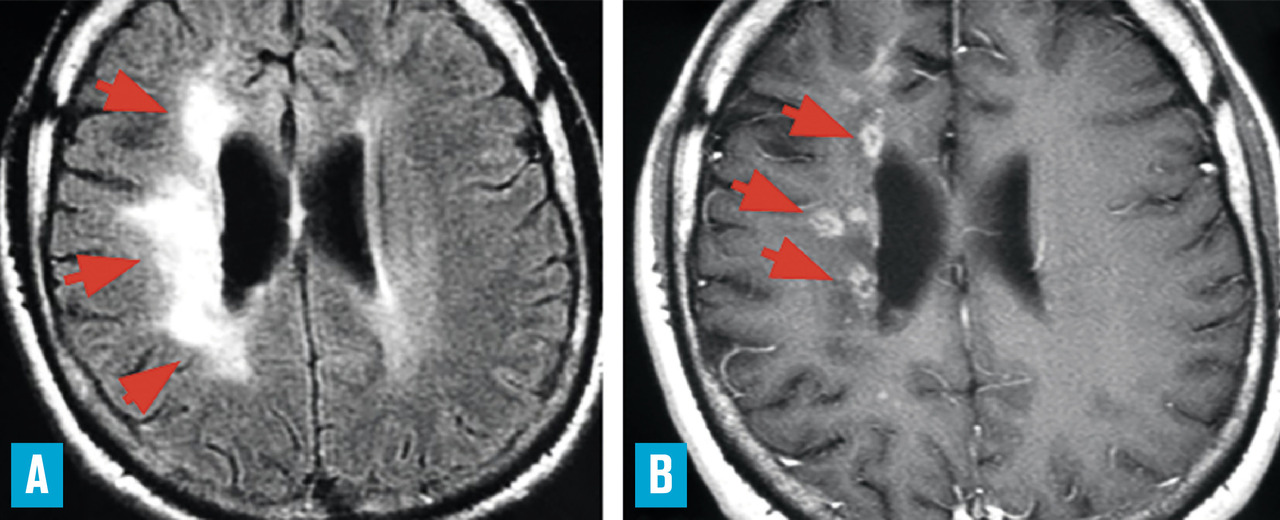

La tomodensitométrie n’a que peu d’intérêt tant sa sensibilité et sa spécificité sont faibles. L’imagerie par résonance magnétique (IRM) est donc indispensable. Aucune anomalie n’est spécifique, mais leur combinaison renforce la suspicion de vascularite (– de lésions parenchymateuses multiples : infarctus corticaux ou profonds dans des territoires différents, hémorragies cérébrales symptomatiques ou non (« microbleeds »), anomalies confluentes de la substance blanche ;

– de prises de contraste corticales et surtout leptoméningées, témoignant de l’atteinte inflammatoire (

Des présentations radiologiques trompeuses ont été rapportées, telles qu’une large lésion unique d’aspect pseudotumoral, ou encore un aspect de leucoencéphalopathie postérieure. La sensibilité élevée de l’IRM pour déceler des anomalies intracérébrales de petite taille peut être source de difficulté : la présence d’hypersignaux de la substance blanche en séquences T2/FLAIR (leucoaraïose), fréquente dans de nombreuses circonstances, ne doit pas être interprétée trop facilement comme étant un signe de vascularite. Outre les signes parenchymateux sus-décrits, il peut exister en séquence FLAIR (sans injection) une hyperdensité d’artères corticales, témoignant d’un ralentissement circulatoire du fait de sténoses distales. L’exploration parenchymateuse est complétée par une angiographie par résonance magnétique (ARM) intracrânienne pour étudier le polygone de Willis et les premiers centimètres de ses branches de division (